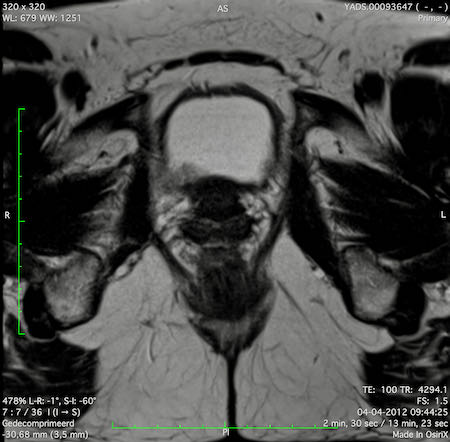

Hình ảnh

Các hình ảnh được cung cấp cho thấy ung thư biểu mô tế bào nhẫn với tình trạng dày lan tỏa thành trực tràng, hình ảnh bia bắn điển hình, và sự xâm lấn mỡ mạc treo trực tràng.